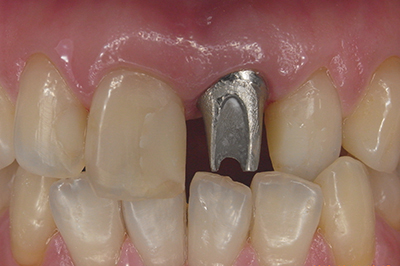

治療例2

歯ぐきが安定した状態

土台をたてた

噛める機能を回復

| ご費用 | 手術費用人工歯根 1本275,000円(税込) 上部構造 88,000円~110,000円(税込) |

|---|---|

| リスク・副作用 | 保険非適応(自費診療) 特定の全身疾患や持病のある方、顎骨密度の足りない方、妊娠中の方は手術ができない場合があります。 下顎のインプラント手術の際、偶発症のリスクがあります。 人工歯根が顎骨と癒着しないリスクがあります。 インプラント周囲炎になるリスクがあります。 |